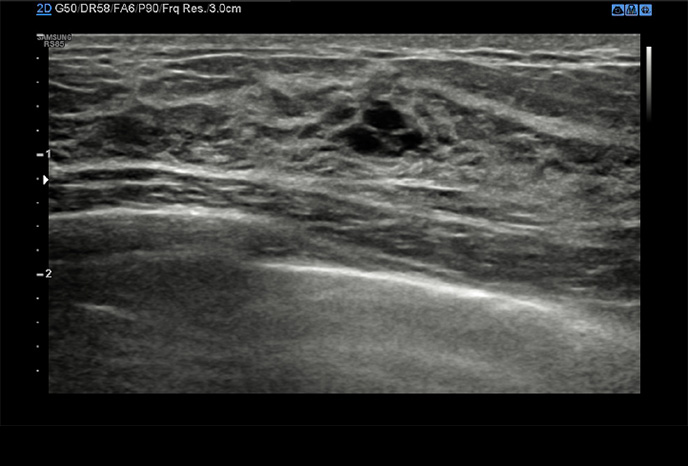

S-Detect™ for Breast

Poloautomatický nástroj pro hodnocení prsou

Funkce, která analyzuje vybrané léze v ultrazvukovém vyšetření prsou a poskytuje analytická data. Pro poskytnutí standardizovaného reportu využívá BI-RADS ATLAS * (Breast Imaging-Reporting and Data System, Atlas). Tím usnadňuje a zrychluje pracovní postup.

S-Detect™ for Thyroid

Poloautomatický nástroj pro hodnocení štítné žlázy

Nástroj, který analyzuje vybrané léze v ultrazvukovém vyšetření štítné žlázy a poskytuje analytická data. Poskytuje standardizovaný report založený na normách *ATA, BTA, EU-TIRADS, K-TIRADS and ACR TI-RADS a pomáhá tím zrychlit a zjednodušit pracovní postup